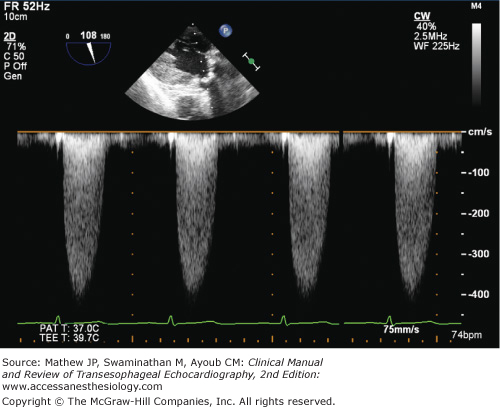

In order to measure transvalvular blood velocity, continuous-wave Doppler (CWD) is used in either the TG LAX or deep TG LAX view. The CWD cursor is aligned with the narrow, turbulent, high-velocity jet and the spectral Doppler display is activated. Accurate localization provides a distinctive high-velocity (>3 m/s) spectral Doppler recording that exhibits a fine feathery appearance and a midsystolic peak (Figure 9–12). Planimetry of the spectral envelope yields the velocity-time integral and an estimate of mean aortic valve gradient. The mean gradient is a derived measurement obtained by all ultrasound systems by averaging the instantaneous gradients over the entire ejection period. The peak pressure gradient (also provided by all ultrasound systems) can be estimated from the peak velocity measurement using the simplified Bernoulli equation:

Figure 9-12.

Continuous-wave spectral Doppler velocities through a stenotic aortic valve. The fine feathery appearance of the high velocities with a mid-systolic peak indicates flow through a stenotic aortic valve. The denser lower velocities near the baseline indicate flow through the left ventricular outflow tract.

Peak gradients are calculated from velocity information and therefore do not provide additional clinical information in comparison to peak velocity. A peak velocity greater than 4 m/s and a mean gradient greater than 40 mm Hg are suggestive of severe aortic stenosis (Table 9–1).